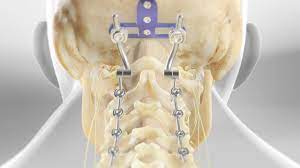

OCCIPITO CERVICAL FUSION

Occipitocervical fusion (OCF) is indicated for instability at the craniocervical junction (CCJ). Numerous surgical techniques, which evolved over 90 years, as well as unique anatomic and kinematic relationships of this region present a challenge to the neurosurgeon. The current standard involves internal rigid fixation by polyaxial screws in cervical spine, contoured rods and occipital plate. Such approach precludes the need of postoperative external stabilization, lesser number of involved spinal segments, and provides 95-100% fusion rates. New surgical techniques such as occipital condyle screw or transarticular occipito-condylar screws address limitations of occipital fixation such as variable lateral occipital bone thickness and dural sinus anatomy. As the C0-C1-C2 complex is the most mobile portion of the cervical spine (40% of flexion-extension, 60% of rotation and 10% of lateral bending) stabilization leads to substantial reduction of neck movements. Preoperative assessment of vertebral artery anatomical variations and feasibility of screw insertion as well as visualization with intraoperative fluoroscopy are necessary. Placement of structural and supplemental bone graft around the decorticated bony elements is an essential step of every OCF procedure as the ultimate goal of stabilization with implants is to provide immobilization until bony fusion can develop.